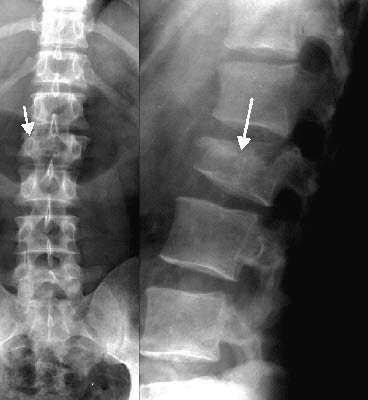

이런 단독사고시 주로 발생하는 상해는 척추압박골절인데요

척추는 일반 팔, 다리의 뼈와는 달리

수직압박손상이나 굴곡, 신전, 신연력에 의한 손상시

척추체가 주저앉으며 골절되는 "압박골절"이라는 형태가 주로 발생합니다.

이는 척추에서만 볼수있는 고유의 골절형태로

방사선검사나 자기공명영상 검사상[MRI]

척추의 본래 형태인 직사각형이 아닌

쇄기모양[사다리꼴]을 나타내게 됩니다.